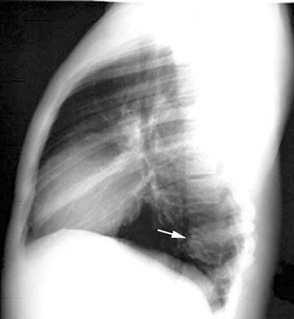

Tuberculosis Spine

Loss of intervertebral space and collapse of vertbra is visible. Click the image on the left to see a close up.